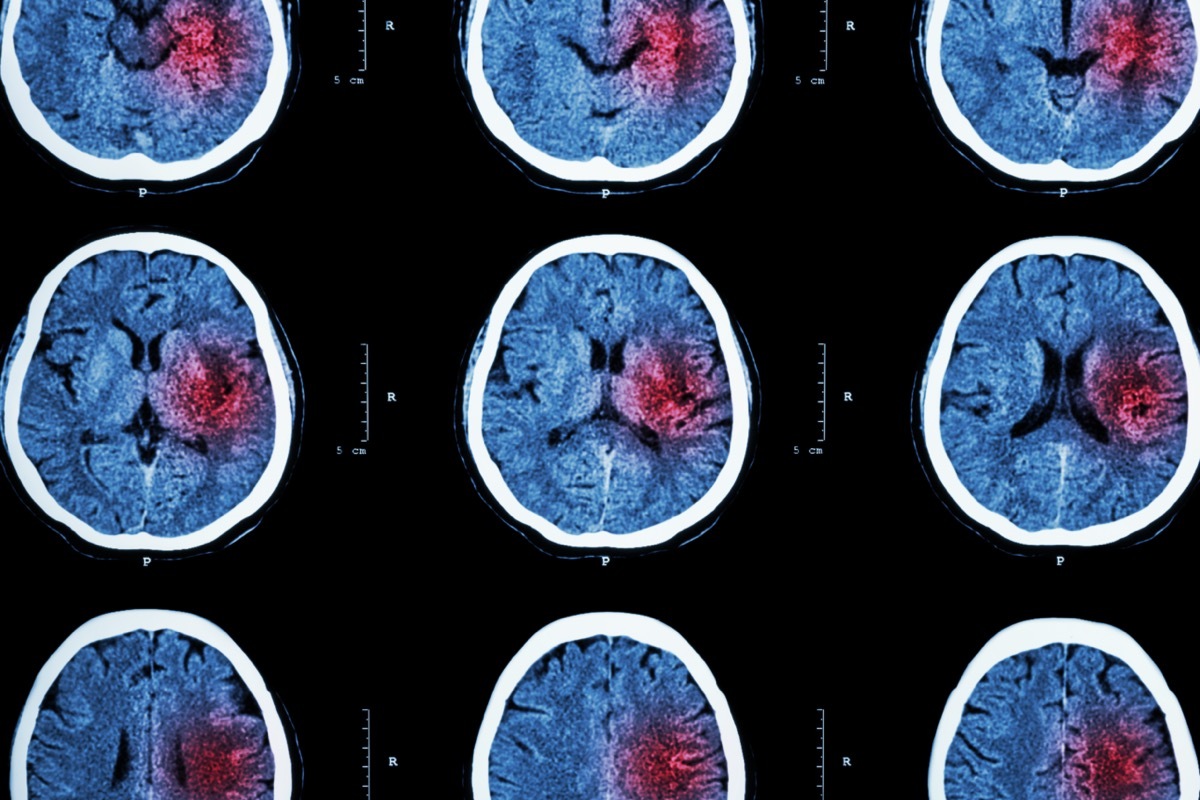

Ein Schlaganfall, manchmal als Hirnangriff genannt, tritt infolge eines von zwei Ereignissen auf,Farhad Bahrassa, MD, Yale Medicine NeuroSurgon und Assistant Professor an der Yale School of Medicine, erklärt dazuEssen Sie das, nicht das! "Ein Schlaganfall ist ein medizinischer Notfall, in dem eine plötzliche Änderung der Gehirnfunktion in der Regel aufgrund einer plötzlichen Abnahme der Blutversorgung zu einem Teil des Gehirns besteht, aber manchmal liegt es an der Blutung im Gehirn", sagt er.

Wenn Sie einen Schlaganfall haben, "der Mangel an Blutversorgung verhindert Nährstoffe und Sauerstoff von dem Teil des Gehirns, erklärt Dr. Bahrassa. "Die Gehirnzellen hören auf, funktionieren und können schnell ohne Sauerstoff und Nährstoffe sterben." Pro CDC gibt es zwei Arten von Schlägen, von denen beide Gehirnzellen beschädigen, und symptomen, dass Symptome in den Körperteilen dieser Gehirnzellensteuerung zeigen.

Ischämischer Schlaganfall: Dieser Typ tritt auf, wenn Blutgefäße an dem Gehirn von Blutgerinnseln oder anderen Partikeln blockiert sind.

Hämorrhagischer Schlaganfall: Ein hämorrhagischer Hub ist das Ergebnis eines Blutgefäßes, das im Gehirn platzt. "Blut baut sich auf und schädigt das Gehirngewebe um," die CDC erklärt.